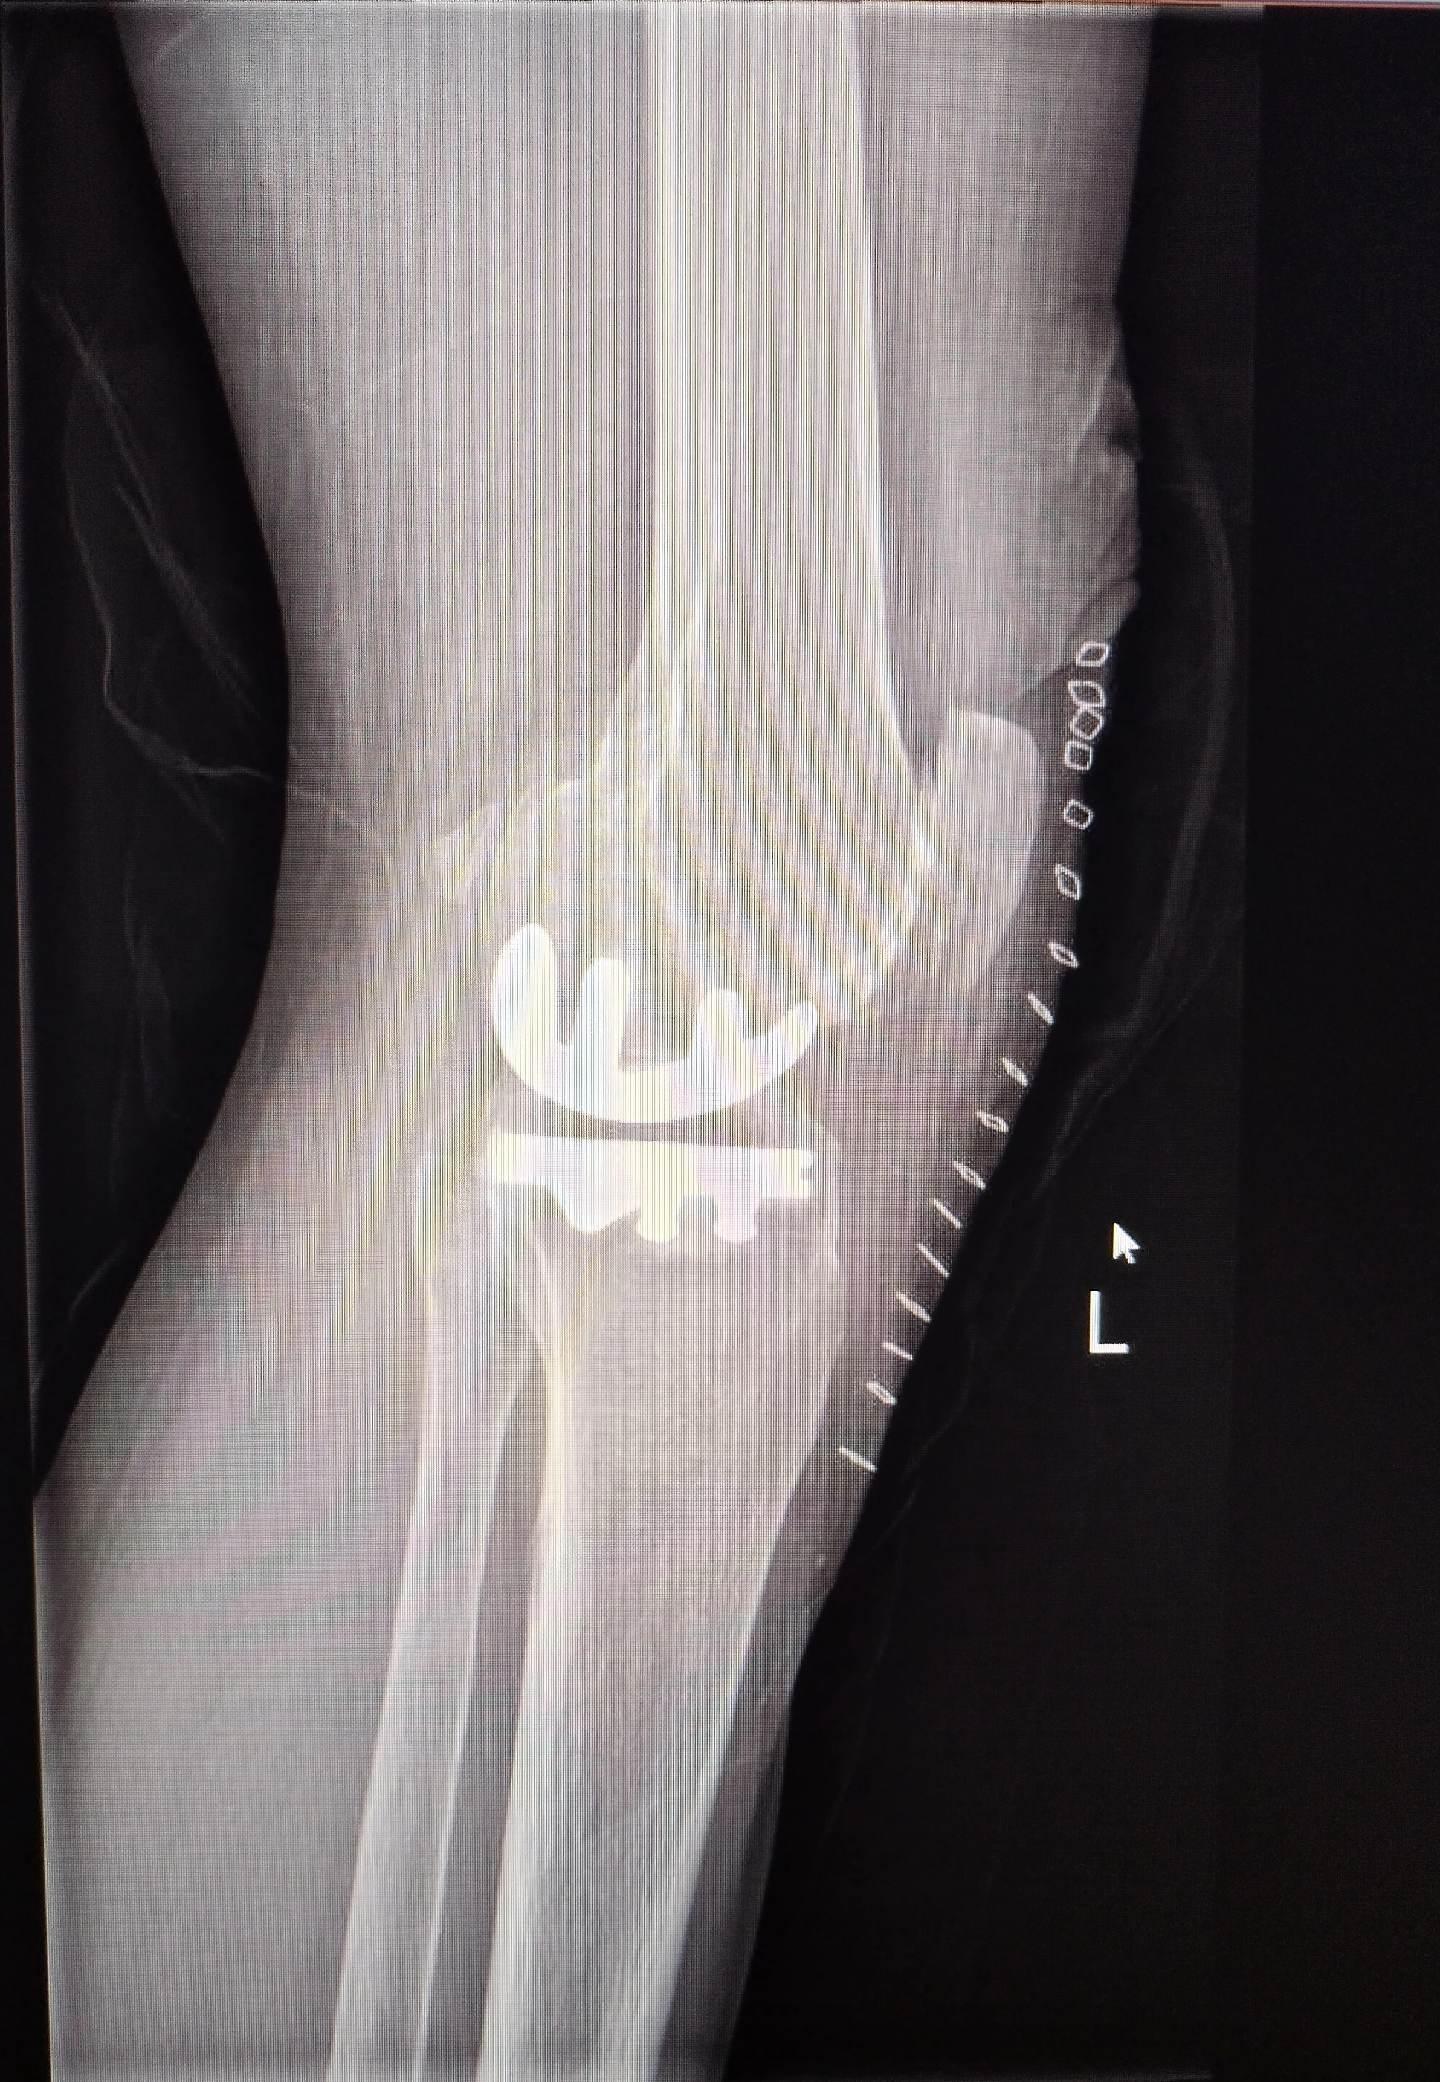

UKA单髁置换。膝关节骨关节炎,同期双侧单髁置换,术后四天出院,快速康复,省医关节外科🌹